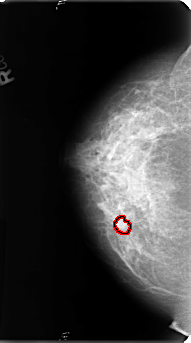

B_3128_1.RIGHT_MLO

RIGHT_MLO LINES 4776 PIXELS_PER_LINE 2768 BITS_PER_PIXEL 12 RESOLUTION 50 OVERLAY

FILE: B_3128_1.RIGHT_MLO.OVERLAY

TOTAL_ABNORMALITIES 1

ABNORMALITY 1

LESION_TYPE MASS SHAPE IRREGULAR MARGINS ILL_DEFINED-SPICULATED

ASSESSMENT 4

SUBTLETY 3

PATHOLOGY BENIGN

TOTAL_OUTLINES 1

BOUNDARY